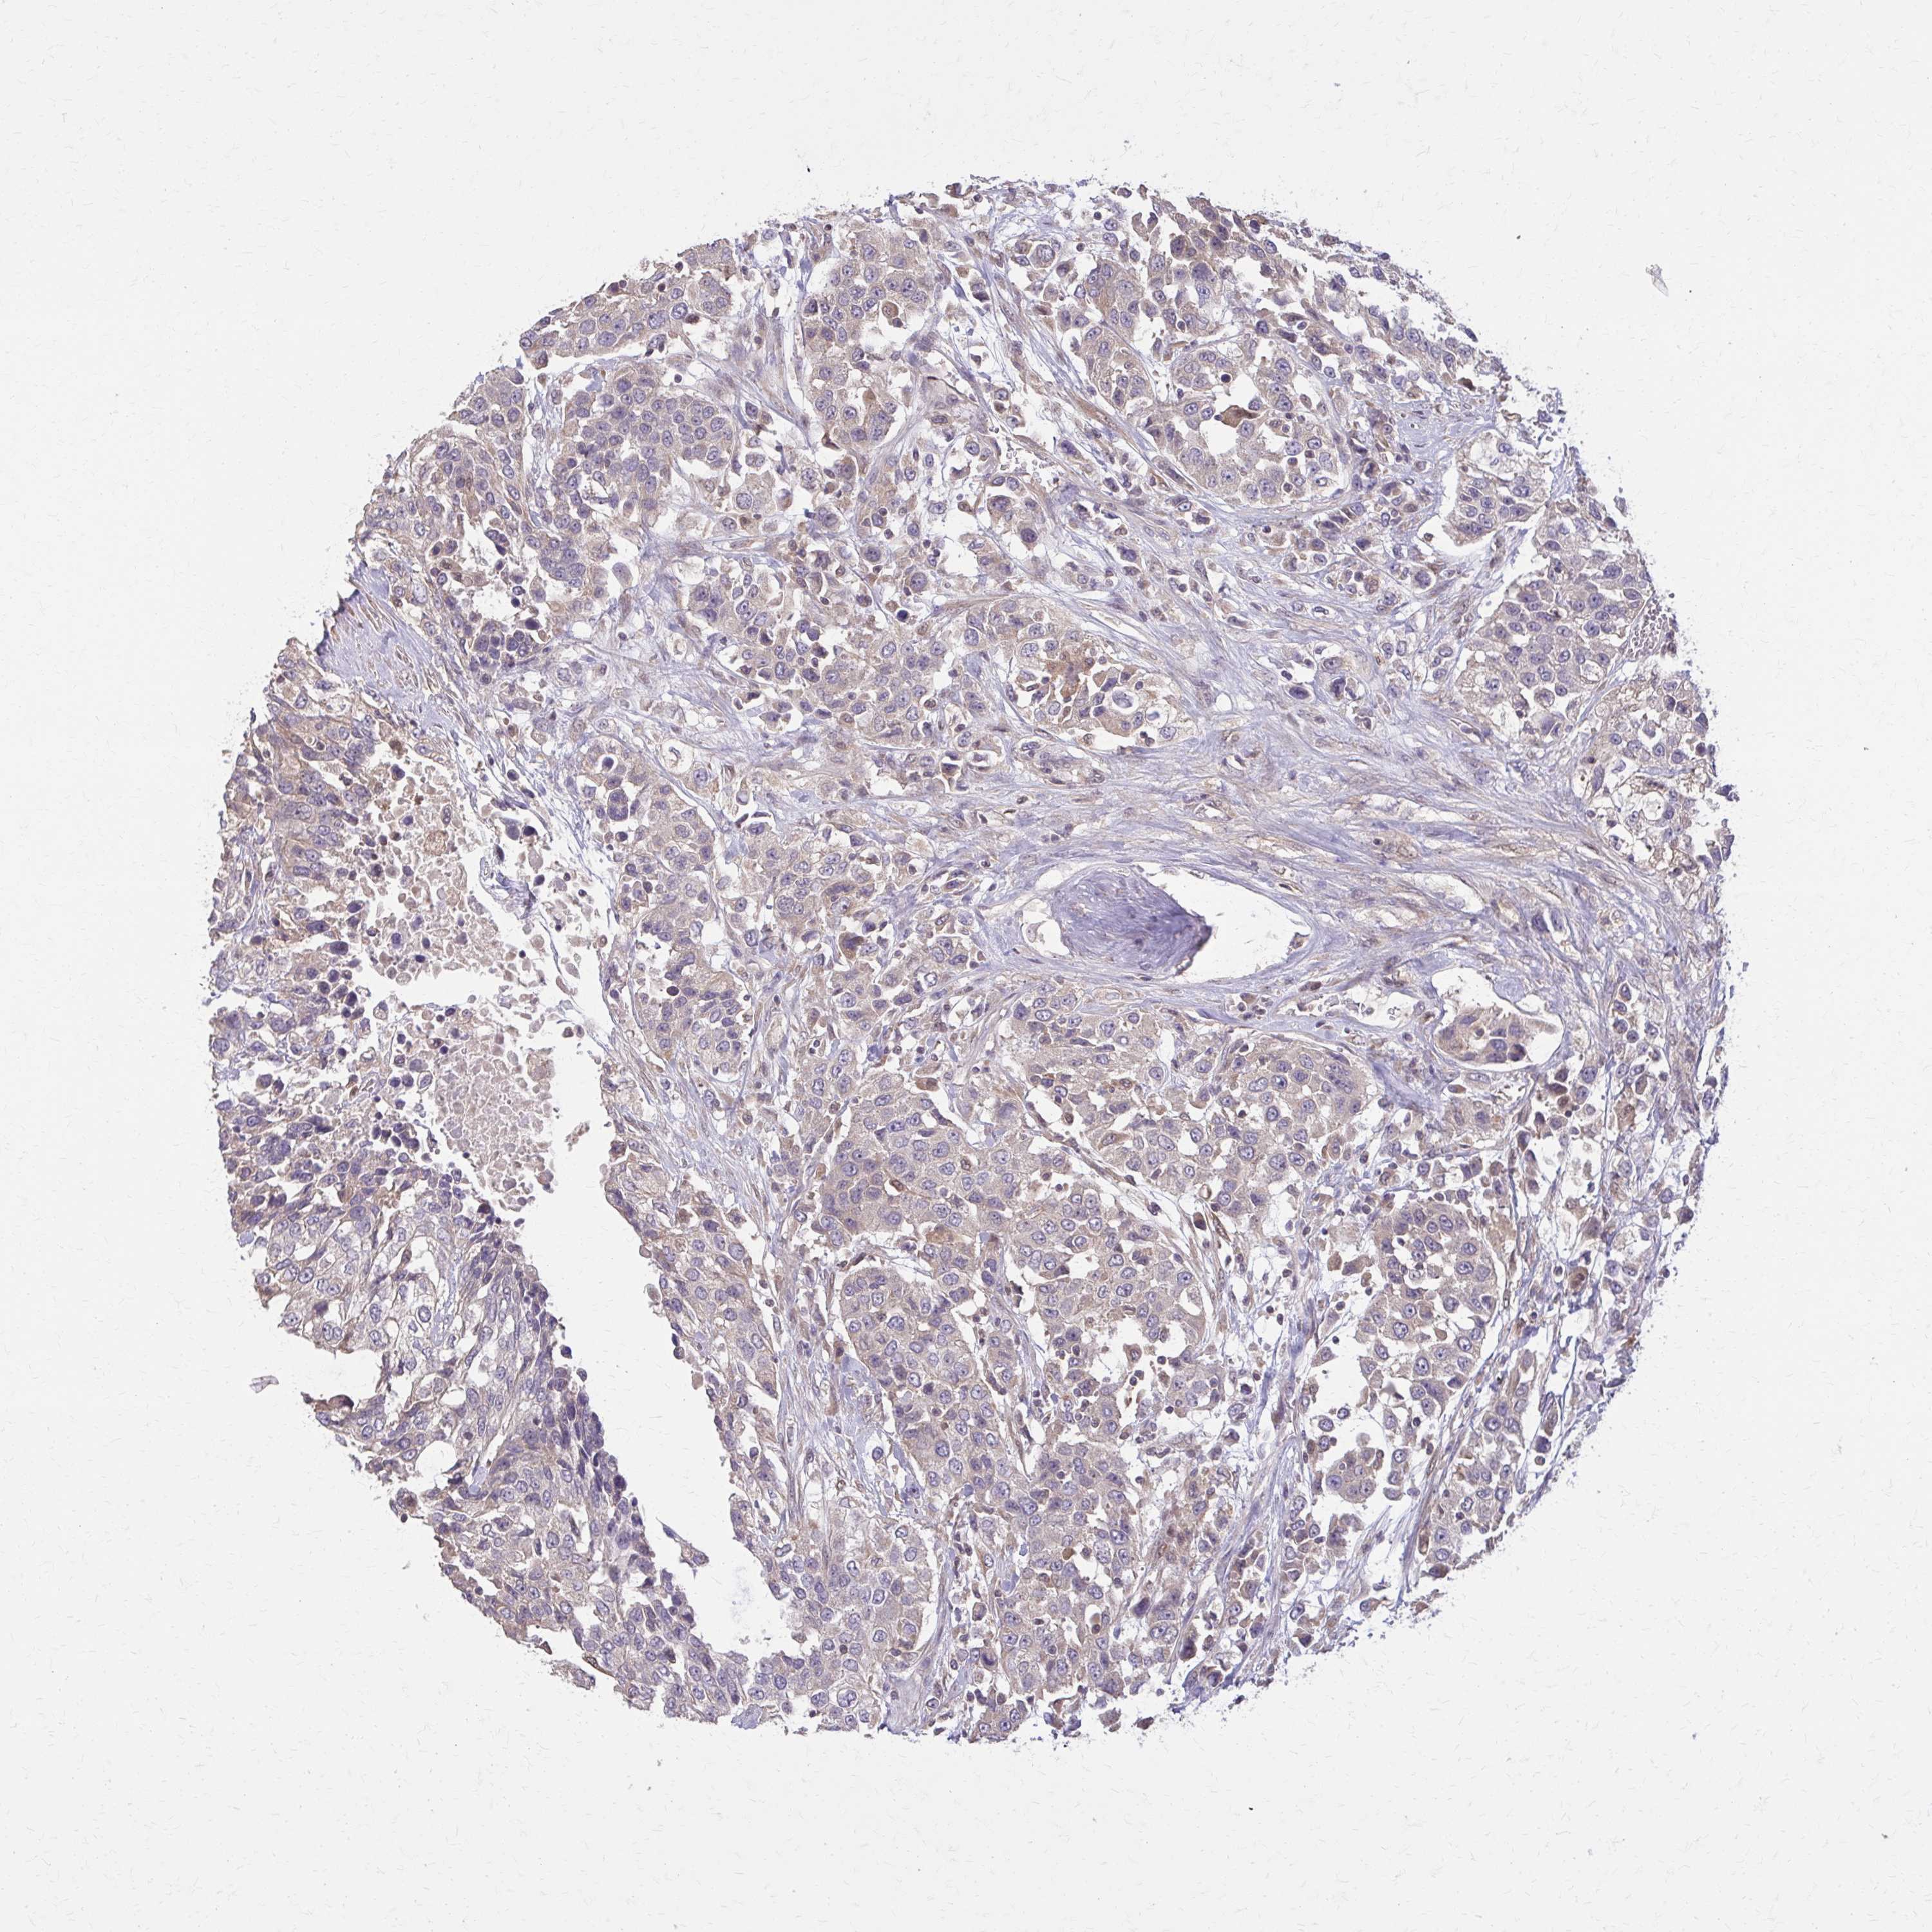

UROTHELIAL CANCER - Protein expressioni

A mouse-over function shows sample information and annotation data. Click on an image to view it in a full screen mode. Samples can be filtered based on level of antibody staining by selecting one or several of the following categories: high, medium, low and not detected. The assay and annotation is described here.

Note that samples used for immunohistochemistry by the Human Protein Atlas do not correspond to samples in the TCGA dataset.

Antibody stainingi

Antibody staining in the annotated cell types in the current human tissue is reported as not detected, low, medium, or high, based on conventional immunohistochemistry profiling in selected tissues. This score is based on the combination of the staining intensity and fraction of stained cells.

Each image is clickable and will lead to virtual microscopy that enables deeper exploration of all samples and also displays staining intensity scores, fraction scores and subcellular localization as well as patient and tissue information for each sample.

Antibody HPA021670

Antibody HPA059477

Urothelial carcinoma, High grade

Urothelial carcinoma, Low grade